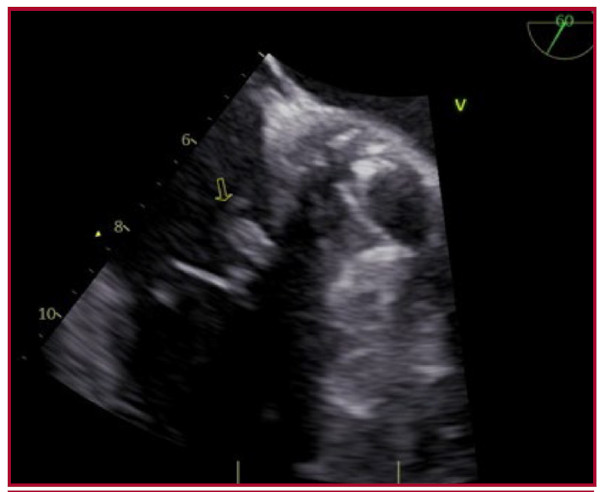

A la semana reingresa por fiebre y decaimiento general; se constata mayor prolongación del intervalo PR en el ECG, de 270 mseg (Figura 1A). En la analítica: leucocitos 11 870/mm3 (neutrófilos 87%, linfocitos 4,7%), proteína C reactiva 25,6 mg/L, procalcitonina 0,19 ng/mL, eritrosedimentación 32 mm/h. Se toman nuevos hemocultivos, donde se aísla Staphilococcus Aureus metilicilino sensible. Se realiza ecocardiografía transtorácica, que revela imagen con movilidad independiente a nivel de la válvula tricúspide, de 0,6 cm x 0,6 cm. Se corrobora en el ecocardiograma transesofágico (ETE) una vegetación de 0,9 cm por 0,6 cm a nivel de la valva septal, insuficiencia tricuspídea leve y válvula protésica normofuncionante (Figura 2).